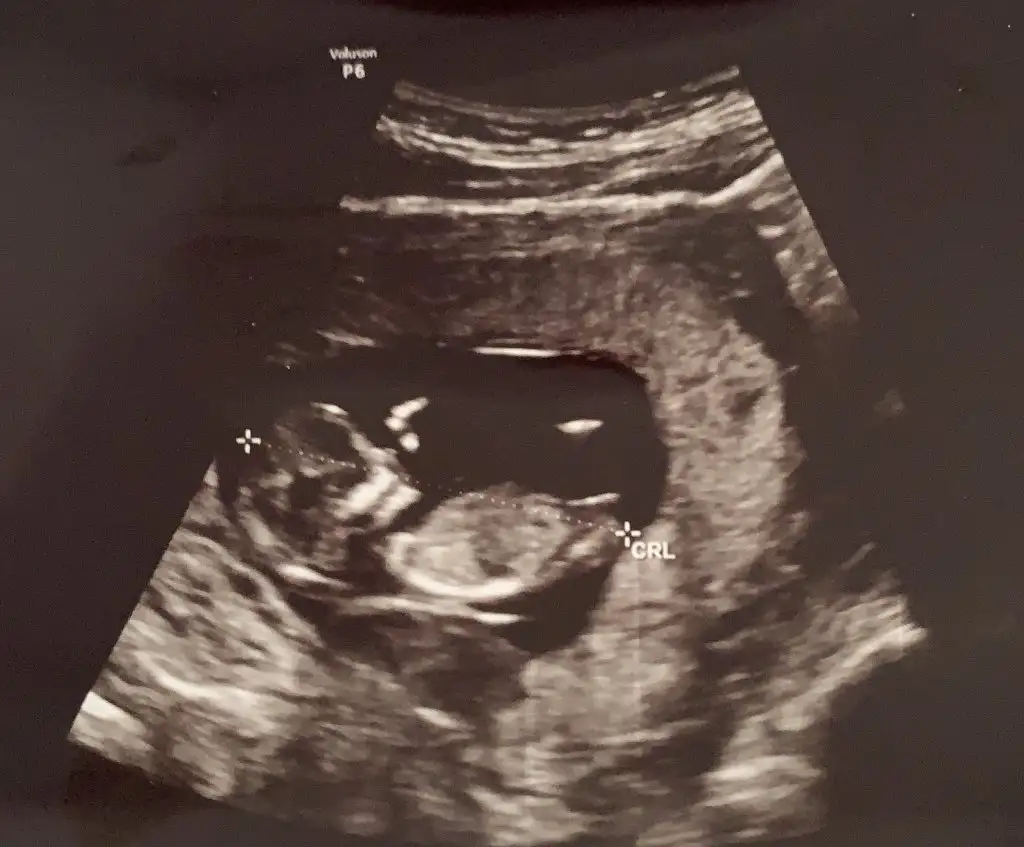

Kız diyorlarda en iyi nub 11 12 13 hafta USG paylasin

15+ da nub olmaz boş görünüyor sanki kız gibi 11 12 13 haftalar olmalı nub icin

...Ikra meyra Merhabaa bana da tahmin yapabilir misiniz?

Kız gibi geldi banaIkra meyra Merhabaa bana da tahmin yapabilir misiniz?